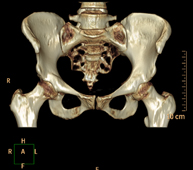

- TC Pelvis ósea Exploración radiológica que mediante un sistema de rayos X y detectores que giran alrededor del paciente, reconstruyendo las imágenes por ordenador (TC Multidetector), permite el estudio de huesos, músculos y articulaciones de la pelvis. Exploración radiológica que mediante un sistema de rayos X y detectores que giran alrededor del paciente, reconstruyendo las imágenes por ordenador (TC Multidetector), permite el estudio de huesos, músculos y articulaciones de la pelvis.

- TC Caderas Exploración radiológica que mediante un sistema de rayos X y detectores que giran alrededor del paciente, reconstruyendo las imágenes por ordenador (TC Multidetector), permite el estudio de huesos, músculos y articulaciones de la cadera. Exploración radiológica que mediante un sistema de rayos X y detectores que giran alrededor del paciente, reconstruyendo las imágenes por ordenador (TC Multidetector), permite el estudio de huesos, músculos y articulaciones de la cadera.

- TC Sacroilíacas Exploración radiológica que mediante un sistema de rayos X y detectores que giran alrededor del paciente, reconstruyendo las imágenes por ordenador (TC Multidetector), permite el estudio de las articulaciones sacroiliacas, y descartar enfermedades inflamatorias, traumáticas o degenerativas. Exploración radiológica que mediante un sistema de rayos X y detectores que giran alrededor del paciente, reconstruyendo las imágenes por ordenador (TC Multidetector), permite el estudio de las articulaciones sacroiliacas, y descartar enfermedades inflamatorias, traumáticas o degenerativas.